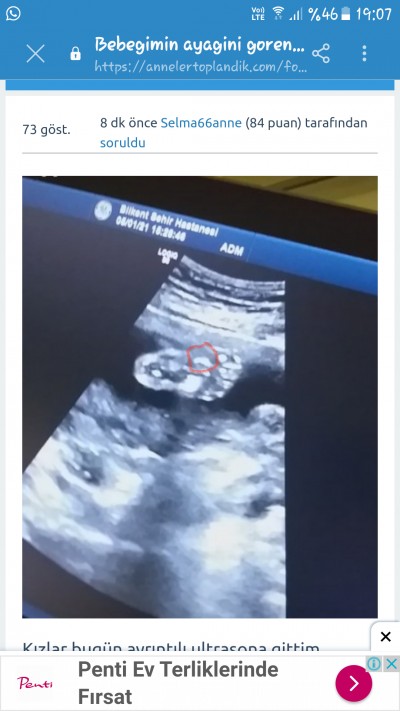

resim çok net olmamış ama gorebildigim kadariyla bitanesi burda

Goruntude govdesi ve kafasi var cok yakindan cektigi icin bacaklarini almamis

Dikkatli bak sadece ayagi ve ayak parmakları var:)) paşamın